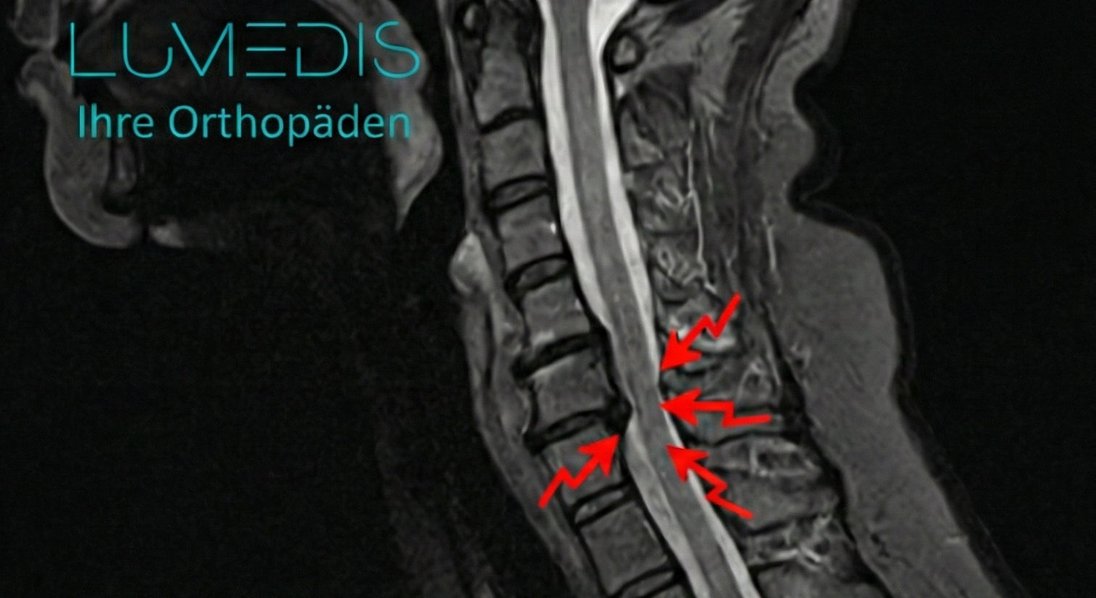

MRT einers Bandscheibenvorfalls der HWS (seitliche T2 Aufnahme):

MRT der HWS seitlich T2

MRT einer HWS mit Spinalkanalstenose

MRT einer Spinalkanalstenose der HWS

MRT einer Spinalkanalstenose der HWS C5/C6 (rote Pfeile)